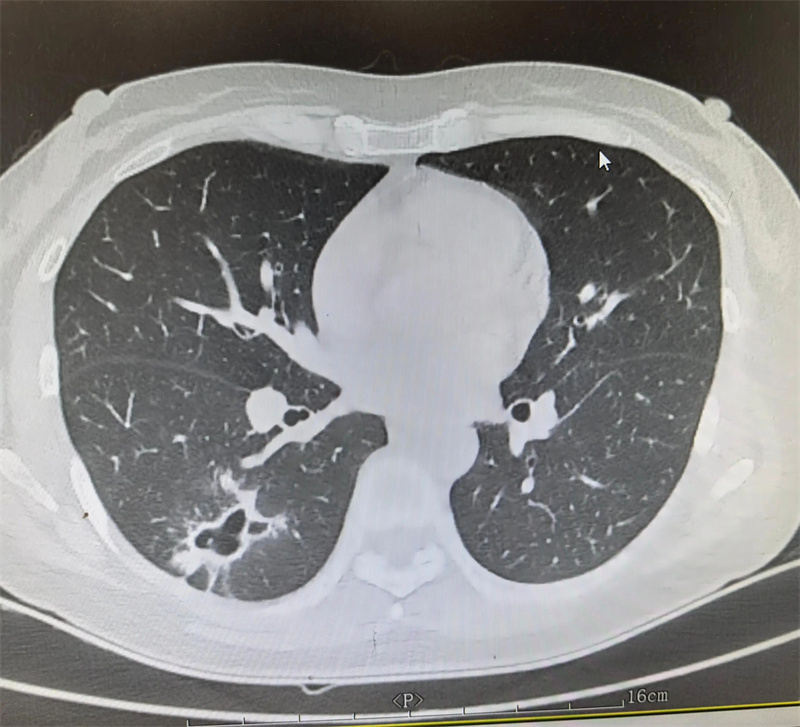

胸外科(二疗区)主任田子刚受邀参与,结合艾利影像学检查、肺功能评估及全身基础状况,与孙集思主任团队反复研讨手术指征、手术方式及围手术期风险防控要点。经过充分论证,最终确定实施“右肺下叶切除手术”。

△图片非案例所提及